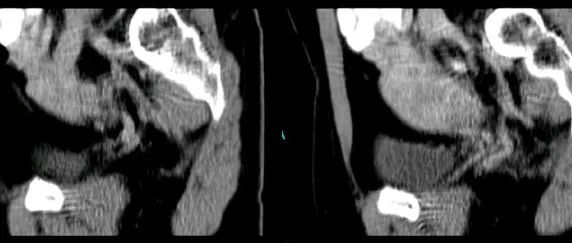

医学影像 yxyx-app 医学影像APP,打造伴随医生快速成长的影像学习社区。与影像园(Xctmr.com)一起提供最全面的影像案例库、基础(解剖、病理、影像诊断)知识、影像技术及考题等,为医生提供最佳的医学影像参考。【所属科室】呼吸科【基本资料】患者,女,20岁【主诉】干咳伴胸痛半月【影像图片】【讨论问题】如何诊断?【医学影像APP用户讨论】评论:左前纵隔见一囊样包块影,内见结节状、条片状脂性密度影,局部囊壁见壁结节影,增强见囊壁及壁结节明显均匀强化;上纵隔脂肪间隙密度增高,但与包块分界尚清,增强后内未见明显强化;肺动脉主干及左侧肺动脉见受压推移,未见充盈缺损影。前纵隔占位,考虑畸胎瘤。...